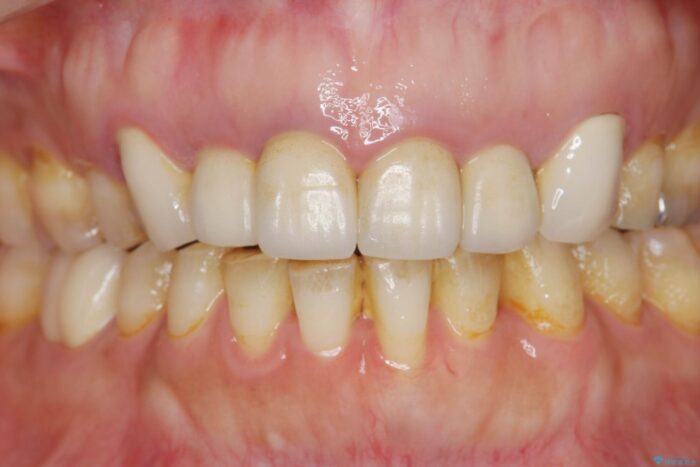

治療計画

装着されていたセラミックを除去したところ、歯ぐきの奥深くまで歯牙は削られ、歯ぐきの炎症・出血が著しくみられる状態でした。

この状態で再度セラミッククラウンの作製・装着を行ってもまた同じ状態となってしまうため、歯周外科を行い歯ぐきの状態を整備したのちセラミッククラウン治療をおこなっていきます。